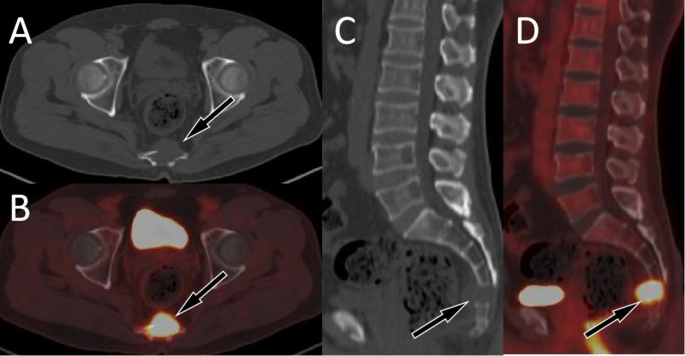

This group of cases includes 22 cases of spinal GCTB, with an average age of 36.3 ± 11.5 years old. There are more male patients than female patients, with 15 males and 7 females respectively. Most of the tumors occurred in the thoracic and sacral vertebrae, with the main body of the lesion located in the vertebral body, showing eccentric, dilatant and lytic bone destruction. Residual bone crista can be seen in it, most of them do not have sclerotic edges, calcification and periosteal reaction, and most of the lesions can break through the bone cortex to form paravertebral soft tissue mass. On PET, these lesions typically present obviously increased 18F-FDG uptake (as shown in Fig. 2), with an average SUVmax of 10.9 ± 4.5. Few PET/CT studies of spinal GCTB have been reported in the literature. A previous research results was consistent with our findings that GCTB showed a higher SUVmax, with a median SUVmax of 9.0 ± 2.0 12. Only a few spinal GCTB lesions are mainly located in the vertebral appendages, with visible sclerotic rim and mildly increased 18F-FDG uptake (Fig. S1).

A 47-year-old woman with typical PET/CT findings of GCTB; (A) Axial CT shows osteolytic bone destruction in the sacral vertebrae, with slightly low-density soft tissue mass formation (arrow); (B) The PET/CT fusion image at the same level shows significantly increased 18F-FDG uptake, with a SUVmax of 12.5; Sagittal (C CT; D PET/CT) shows almost complete dissolution of the affected sacral vertebrae (arrows).